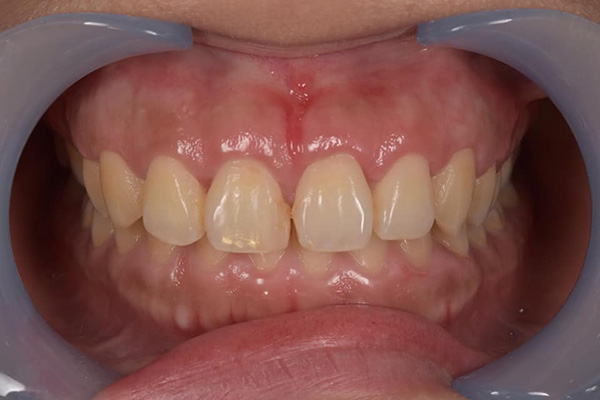

牙周病初期治療(無手術,治療前)![]() |

牙周病初期治療(無手術,治療後)![]() |